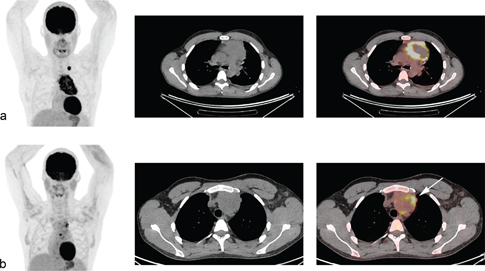

Fig 2

Figure 2. A young woman with a history of progressive swellings, dyspnea, and fever. Biopsy revealed Hodgkin lymphoma. Abnormal FDG-uptake at baseline PET/CT (a,b,c) was confined to enlarged clavicular and mediastinal lymph nodes, i.e., disease stage 2. Interim PET/CT (d,e,f) after two cycles of ABVD (doxorubicin, bleomycin, vinblastine, and dacarbazine) was coherent with complete metabolic response (Deauville Score 2) although lymph nodes remained enlarged on CT scan.

Fig 3

Figure 3. A young woman with Hodgkin lymphoma, stage II. Baseline FDG PET/CT (a). Interim PET/CT (b) performed after two cycles of ABVD (doxorubicin, bleomycin, vinblastine, and dacarbazine,) revealed partial metabolic response with residual FDG-uptake above liver uptake (lymphoma SUVmax=8.6, liver SUVmax=2), classified as DS 4.

A common language for assessing metabolic response by PET/CT is necessary to ensure that the treatment decisions are reproducible. The international harmonization criteria from 2007 proposed a dichotomous scoring system where mediastinal blood pool activity was recommended as the reference background activity to define PET positivity for a residual mass greater or equal to 2 cm in greatest transverse diameter, whereas background update was to be used for assessment of smaller lesions (28). However, dichotomous scores in lymphoma proved suboptimal. Response-adapted treatment strategies based on interim PET/CT should enable tailoring the risk of false positive/false negative assessments to the question being asked in the trial, which can be done using more granular response reporting (29). The Deauville 5-point score (DS) is now the standard for reporting PET/CT response assessment in lymphoma (Figure 2 and 3) (7). DS was conceived to graduate the intensity of 18F-Fluoro-deoxy-glucose (FDG) uptake in previously identified lymphoma lesions relative to the liver uptake. DS 1 and 2 represent a FDG uptake lower than that of liver, uptake DS 3 represents an intensity of uptake up to that of liver, and DS 4 and 5 represent different degrees of FDG uptake above liver level and new lesions (score 5) (7). For interim and end-of-therapy response assessment in HL, a scores between 1 and 3 are conventionally considered as complete metabolic response (Figure 2) whereas DS 4 or 5 represent active HL (Figure 3) (7). Several studies have shown that the Deauville score is high prognostic in HL using DS 1–3 to define a complete metabolic response (CMR) and DS 4–5 as non-response. In two recently finalized trials of PET-guided de-escalation strategies (HD16 and D18) conducted by the German Hodgkin Study Group, the trials were designed to use DS 1–2 (above the mediastinum) as negative (or equivalent), but further analyses of these trials showed that residual uptake above liver level (DS 4–5) was better in predicting outcomes (3032). In the HD16, 5-year PFS was 93.2% among PET-2-negative patients and 88.4% in PET-2-positive patients (P = .047) when using DS3+ as definition of a positive PET/CT, but when using liver cutoff (DS 4+) for PET-2 positivity, 5-year PFS was 93.1% for PET negative patients vs 80.9% for PET positive patients (P = .0011) (30). In post-hoc analyses of HD18, DS4 was the only risk factor for inferior overall survival in a cohort of patients with DS 1–4 after two cycles of BEACOPP escalated after adjustments for other risk factors (32). The timing of interim PET/CT in HL is conventionally after two courses of chemotherapy, but a negative PET/CT after 1 cycle also has a very high negative predictive value (2-year PFS 98%) and is currently used in clinical trials of very early PET/CT adapted treatment strategies (NCT03517137) (33).